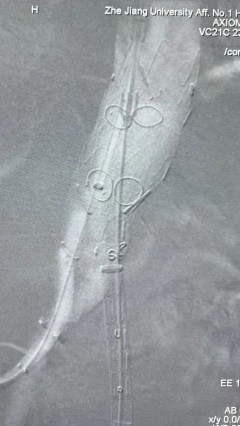

术后评价

G-Branch在本例手术中展示出对扭误会剖结构的杰出适应性,针对该患者严沉扭曲的瘤颈,支架系统的优异柔顺性使其可能顺利通过复杂蹊径,实现内脏分支血管的沉建。

其怪异的双内嵌、双表翻混合多分支设计两全了操作效能与结构靠得住性,预置导丝系统简化了肠系膜上动脉(SMA)撼构腔干动脉(CA)的超选流程,显著提高手术效能。